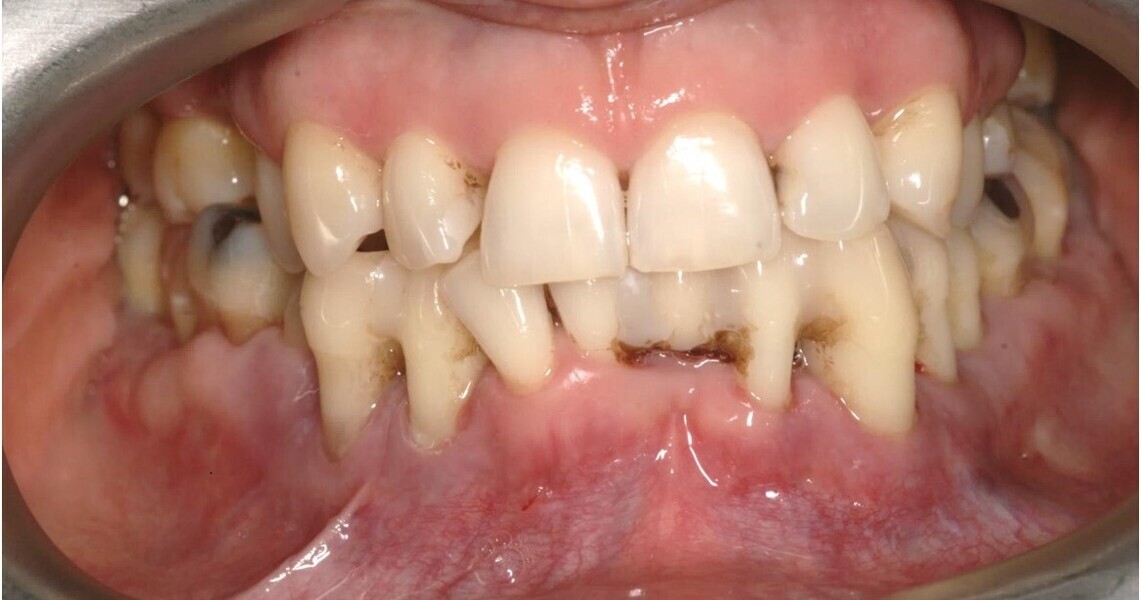

Natychmiastowa implantacja i zaopatrzenie protetyczne pacjentów z zaawansowaną chorobą przyzębia